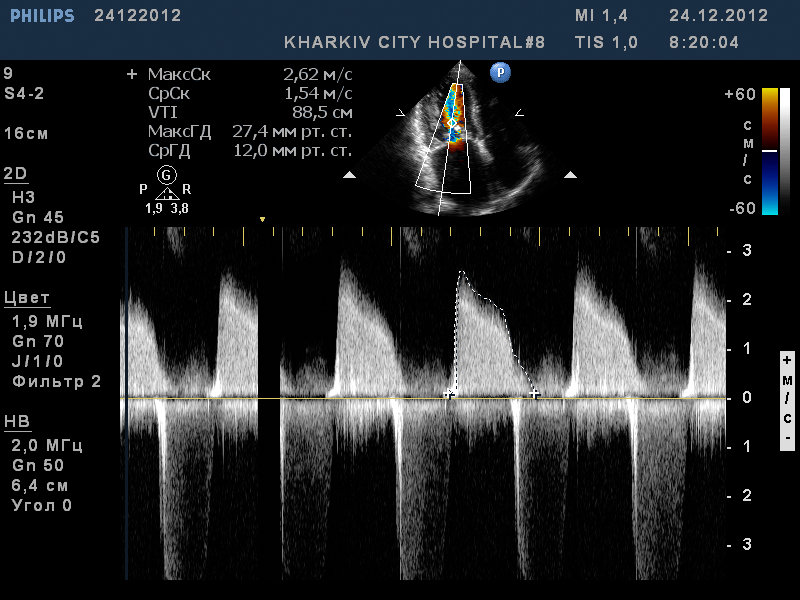

Пациент 52 лет. Поступил с нарушение ритма.

Заключение узи : склеротические изменения аорты, фиброзные изменения створок аортального клапана, незначительная недостаточность аортального клапана, частичный отрыв хорд передней створки митрального клапана, значительный митральный стеноз, умеренная МН, дилатация левого предсердия (6,0см), гипертрофия левого желудочка.

2.jpg